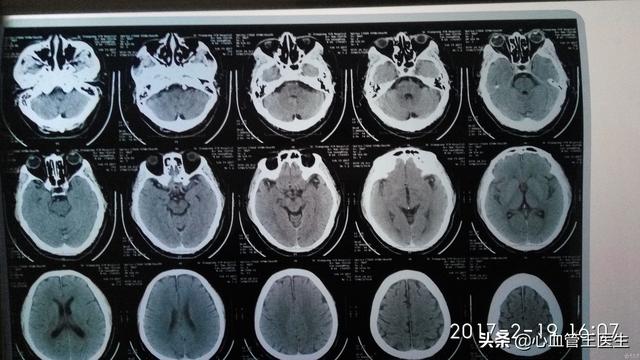

まず脳萎縮≠「アルツハイマー病」(パーキンソン病)である。脳萎縮は別の病気ではなく、客観的な症状、つまりCTなどの画像検査で見られる脳組織の縮小、細胞数の減少、脳室の拡大などの現象で、多くの病気の画像的な現れである。

脳萎縮とは、様々な原因による脳組織自体の器質的な病変により、脳細胞の数や体積が減少し、形態学的に萎縮として現れる現象である。頭蓋CTやMRIでは、脳組織の容積の減少や脳室やクモ膜下腔の拡大が認められることがある。この疾患は50歳以上で発症する傾向があり、数年から数十年続くことがあり、女性よりも男性に多い。

脳萎縮は画像診断の一つであり、CTやMRIで灰白質の減少や溝の深化を認めた場合、画像診断医は「脳萎縮」と診断する。病理学的には、脳萎縮は脳組織の縮小、細胞数の減少、脳室とクモ膜下腔の拡大によって特徴づけられる。脳萎縮は必ずしも病的なものとは限らず、通常は生理的脳萎縮と病的脳萎縮がある。

1.生理的な脳の萎縮 年齢が徐々に高くなるにつれて、ほとんどの人の脳は、特に60歳以上の人は、脳溝の深化と脳回の狭小化によって現れる、さまざまな程度の萎縮が見られるようになる。しかし、これは人間の正常な老化の現れであり、通常、知能や記憶力、計算能力などの特別な低下は見られない。

2.病理学的脳萎縮 病理学的脳萎縮は通常60歳未満で発症し、その原因としては、1.脳卒中、外傷性脳損傷、頭蓋内感染による脳萎縮、2.アルツハイマー病、前頭側頭葉型認知症、ハンチントン病、皮質基底核変性症、多系統萎縮症、進行性核上性麻痺、その他の神経変性疾患による萎縮、3.長期にわたる過度のアルコール摂取、などが挙げられる。